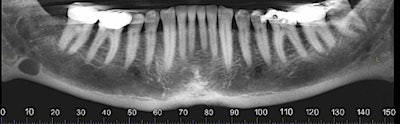

The oral surgeon ordered a cone-beam CT (CBCT) exam. Click images below to enlarge. In order: reformatted panoramic radiograph and cropped image of the area of interest, coronal view of the posterior right mandible (the inferior alveolar canal in red), and 3D reconstructed image of the posterior right mandible.

Figure 3: Coronal view of the posterior right mandible (the inferior alveolar canal is highlighted by red dot).

Figure 4: Coronal view of the posterior right mandible (the inferior alveolar canal highlighted in red) and 3D-reconstructed image of the posterior right mandible.

There is a hypodense lesion (radiolucent) that is well-defined, well-corticated, oval in shape, 8 x 6 mm, located at the posterior right mandible, and distal to tooth #32. The lesion is located below the inferior alveolar canal. No expansion is observed in the cross-sectional views. No calcifications are observed inside the lesion.

From the radiographic perspective, Stafne bone defects are radiolucent lesions, well-defined and well-corticated, oval in shape, and located below the inferior alveolar canal. No expansion is usually observed in the coronal views.

The differential diagnosis includes benign and malignant lesions; however, the location below the inferior alveolar canal is an anatomical landmark that helps to differentiate a Stafne bone defect from odontogenic lesions (usually located above the inferior alveolar canal).